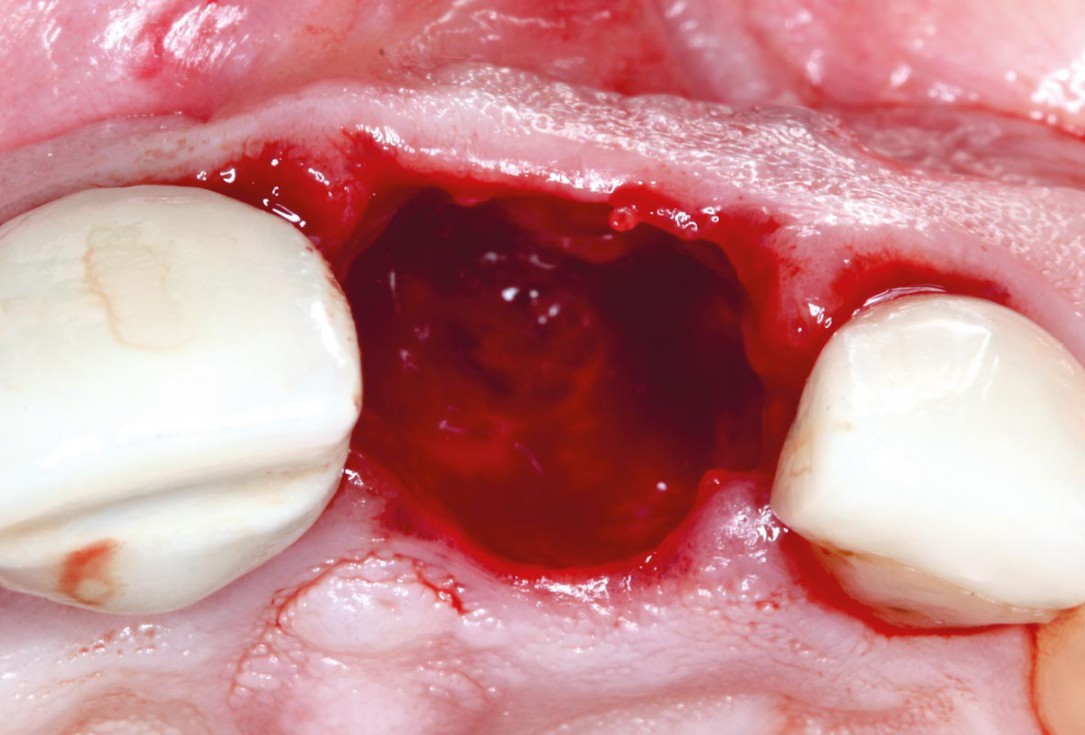

01/10 - Alveolar socket before soft and hard tissue augmentation

Socket augmentation using mucoderm®, maxgraft® and Straumann® Emdogain® - Dr. A. Puišys